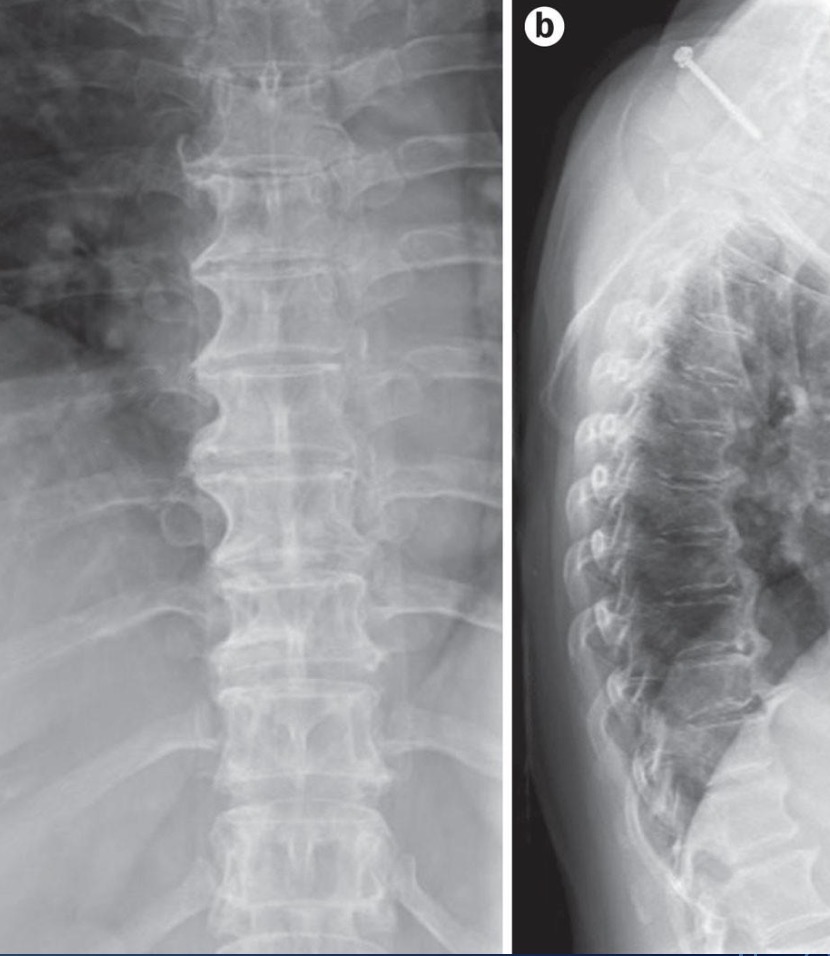

Ankylosing Spondylitis ⭐

Fusion of joints in spine

Vertebral body squaring, shiny corners of squares

Syndesmophytes visible - Bamboo spine

Ossification of interspinous ligaments - Dagger spine